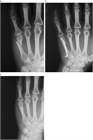

1. 骨折する部位により特徴的な変形を呈する。

1. 関節拘縮を起こさないような内固定と外固定が必要であり、解剖の熟知が重要である。